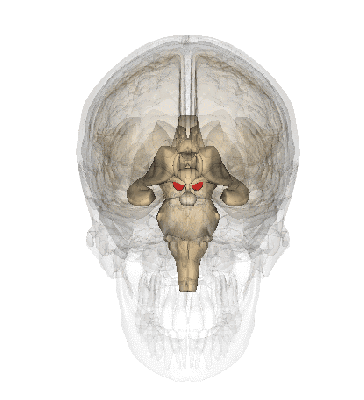

基底核